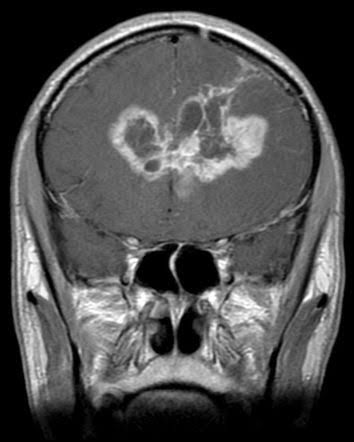

Butterfly glioblastoma (bGBM) is an aggressive form of glioblastoma with bilateral involvement, crossing the corpus callosum to form a butterfly-like tumor [1-3]. Limited literature reports highlight a dismal prognosis with few effective treatment options